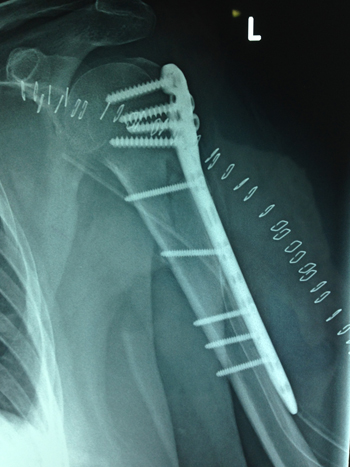

| Συντριπτικό κάταγμα κλείδας | Κάταγμα ώμου |